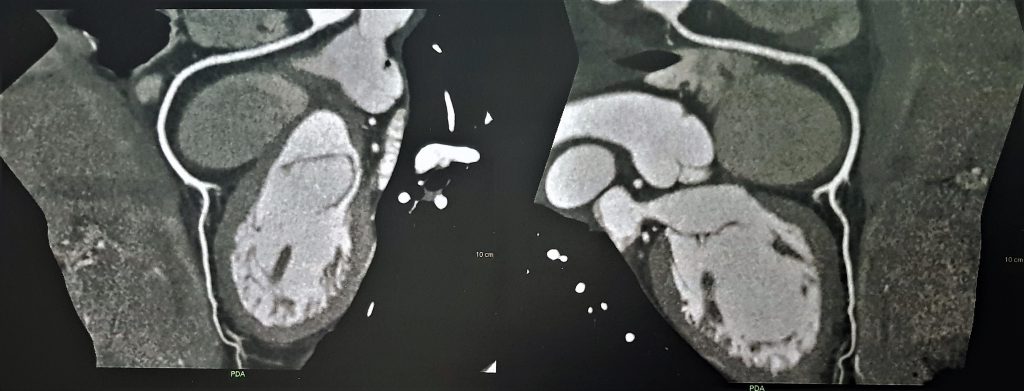

Debido a estos hallazgos se decidió evaluación mediante RMI y TAC. En la TAC multislice cardíaca se descartó la presencia de enfermedad coronaria.

TAC 1

TAC 2

TAC 3